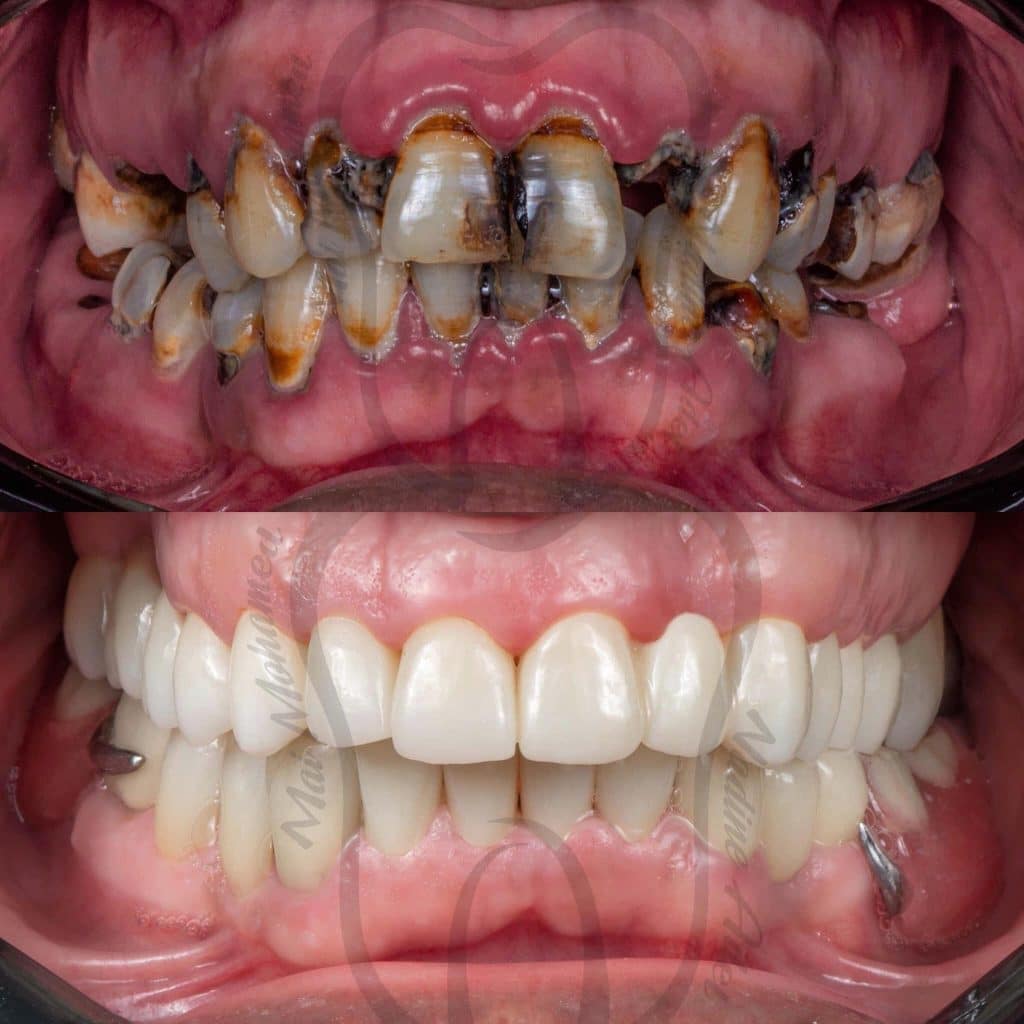

Our treatment plan included:

📌 10 Extractions

📌Full Mouth scaling and Root planing

📌 12 Endodontic treatment

📌 6 Post and Core

📌 Full Mouth Composite Restoration

📌 20 Unit Zirconium

📌 5 Unit PFM

📌 Lower Arch Class I Metallic RPD